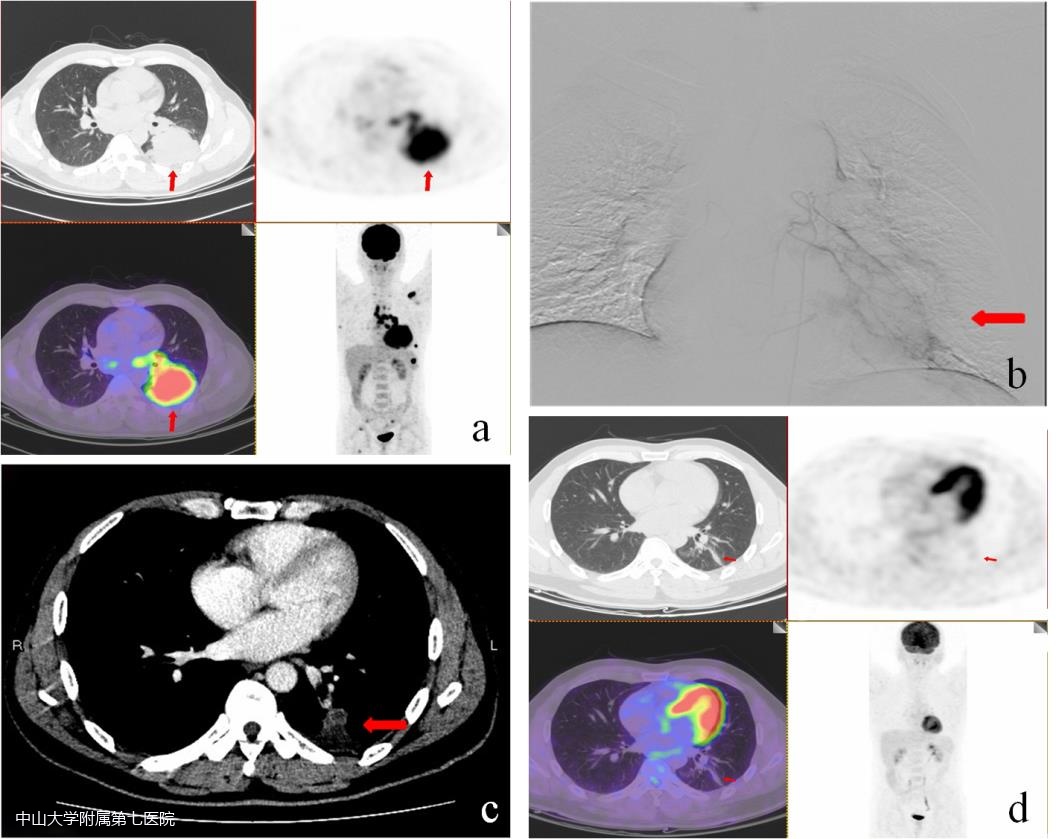

据报道,一名50岁男性左下肺有巨大肿块,伴纵隔肺门多发淋巴结转移,多发骨转移,穿刺病理提示:肺腺癌,EGFR,EX19 Dec (+),T3N3M1,IV期。采用吉非替尼+经动脉灌注化疗联合治疗,一个疗程后即2月后复查CT见肿瘤明显缩小至少70%以上,6月后复查全身PET见肿瘤完全消失,获影像学CR,该患者总生存期达49月。

论文报道的50岁男性病例